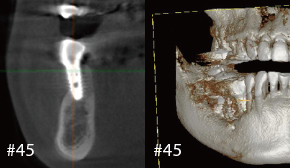

Clinical Case

1. 술전